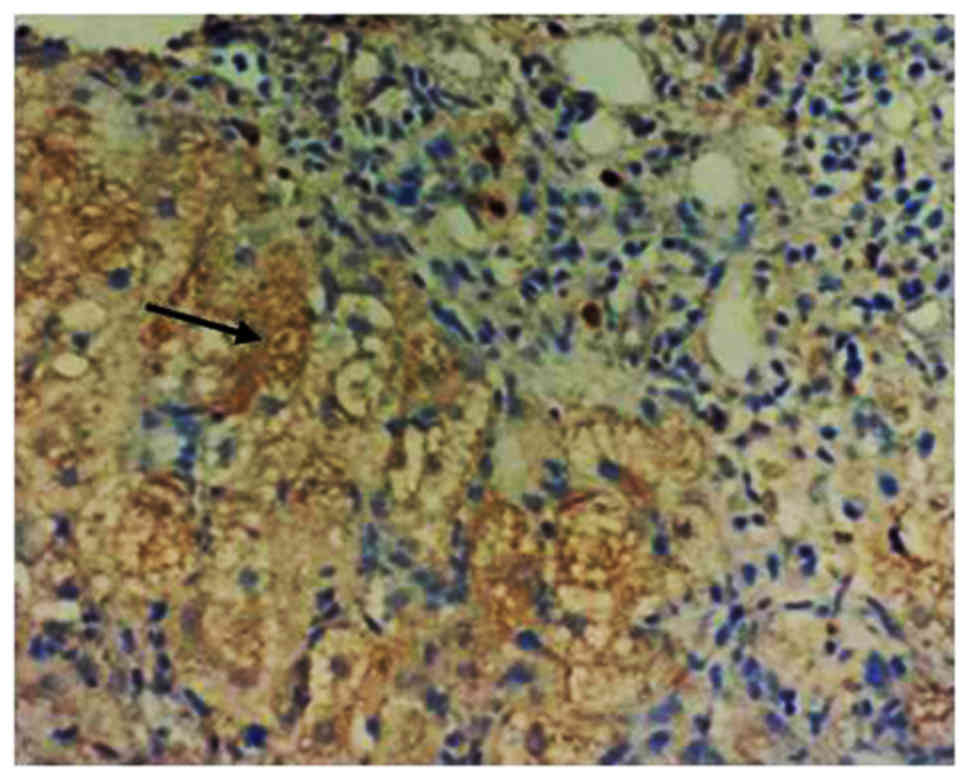

The changes in the levels of pDCs in the response group and non-responders group prior to and after treatment with IFN-α were analyzed. The pDC markers BDCA-2 and ILT7 were detected by IHC analysis, and they were uniformly expressed throughout the cytoplasm of these cells (Fig. 1, arrow). There was no significant difference in amount of pDCs (BDCA-2 and ILT7 expressions) between the response group and the non-responders group prior to IFN-α treatment. After IFN-α treatment, BDCA-2 and ILT7 expression was obviously increased in the response group compared with that in the non-responders group (P<0.05; Fig. 2).

Figure 1.

Representative image for the immunohistochemical detection of blood dendritic cell antigen 2- and immunoglobulin-like transcript 7-positive pDC cells. Positive staining was observed in the cytoplasm (black arrow; magnification, ×100).